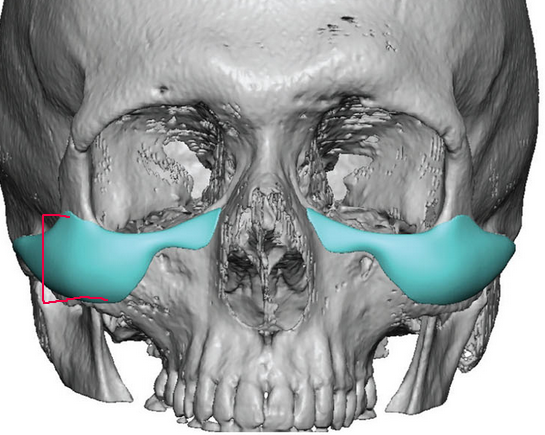

Putting all malar implants in the same category kills all nuance. A lot of malar implants place volume on the lower sections of the zygoma which adds vertical height to the cheekbones which does not look very good. In addition, if you don't have dimorphism in other parts of your face they will looks strange/gay and will throw off harmony. They have to be done right.Malar implants give a very feminine look to the face. On a man it will look very ‘gay-like’. Apple cheek look. Ideal for women maybe but absolutely not for men.

I think he got submalar implants not malarPutting all malar implants in the same category kills all nuance. A lot of malar implants place volume on the lower sections of the zygoma which adds vertical height to the cheekbones which does not look very good. In addition, if you don't have dimorphism in other parts of your face they will looks strange/gay and will throw off harmony. They have to be done right.

Should have looked something like this:

View attachment 4827382

And with dimorphism in other areas:

View attachment 4827387

View attachment 4827389

These are normie implants, you see they are tall and reach the bottom of the zygoma

View attachment 4827391

These type of implants are better as they are higher set and don't increase lower zygomatic protrusion (which is what you want)

Some of those implants can have very different measurements at the upper zygo area vs the lower, so even if the whole implants covers a lot of area, doesnt necessarily mean that there's a lot of projection in the whole areaPutting all malar implants in the same category kills all nuance. A lot of malar implants place volume on the lower sections of the zygoma which adds vertical height to the cheekbones which does not look very good. In addition, if you don't have dimorphism in other parts of your face they will looks strange/gay and will throw off harmony. They have to be done right.

Should have looked something like this:

View attachment 4827382

And with dimorphism in other areas:

View attachment 4827387

View attachment 4827389

These are normie implants, you see they are tall and reach the bottom of the zygoma

View attachment 4827391

These type of implants are better as they are higher set and don't increase lower zygomatic protrusion (which is what you want)